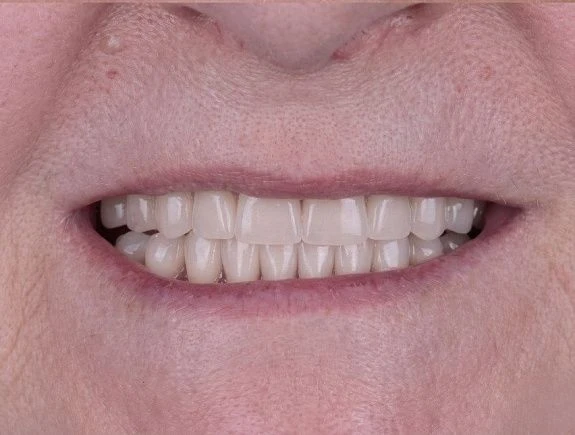

Будет ли заметна разница между Е-max и натуральными зубами при улыбке?

Наши специалисты внимательно подходят к подготовке и подбирают оттенок коронки, идеально повторяющий натуральную эмаль пациента. При правильном изготовлении и установке отличить искусственную коронку от натурального зуба невозможно, и удается полностью восстановить эстетику улыбки.